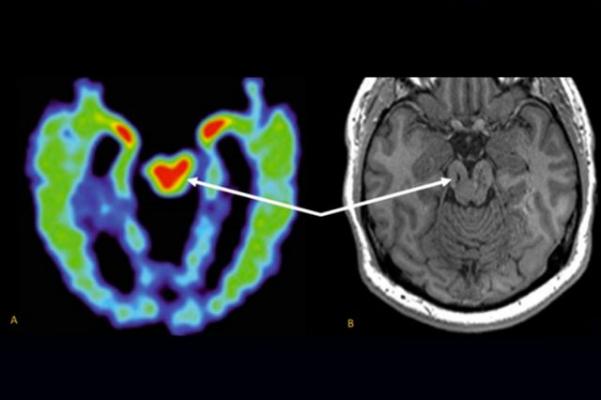

Comparing a PET scan of an NFL player’s brain, left, and an MRI of a former high school football player’s brain shows similar suspected CTE pathology in the midbrain. Image courtesy of UCLA Health

Researchers are trying to develop other methods for diagnosing CTE in the living, including PET scans based on radioactive tracers that bind to tau aggregates. But an MRI-based method, which uses no radioactive materials, would be safer and less expensive, Merrill said.